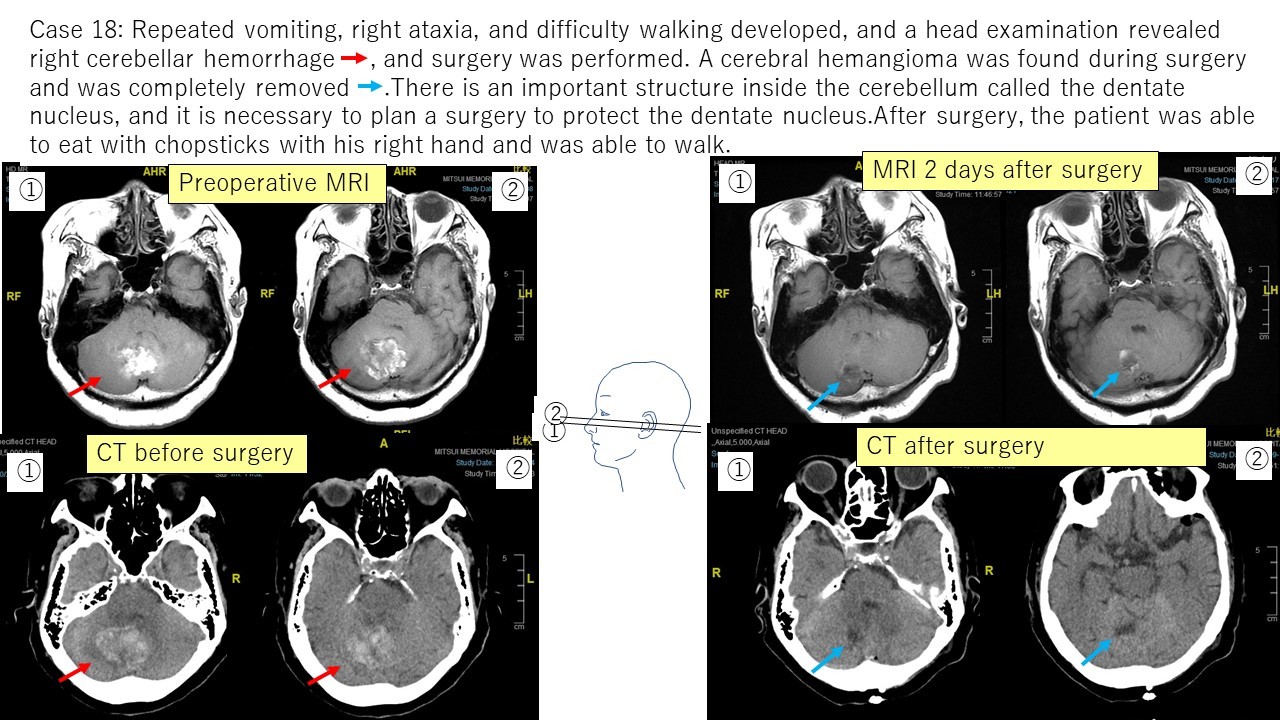

④ Hemangiomas Case 17 Case 18

In this way, I have experienced various neurosurgery operations, and I continue to study every day so that I can provide patients with appropriate diagnoses and treatments.